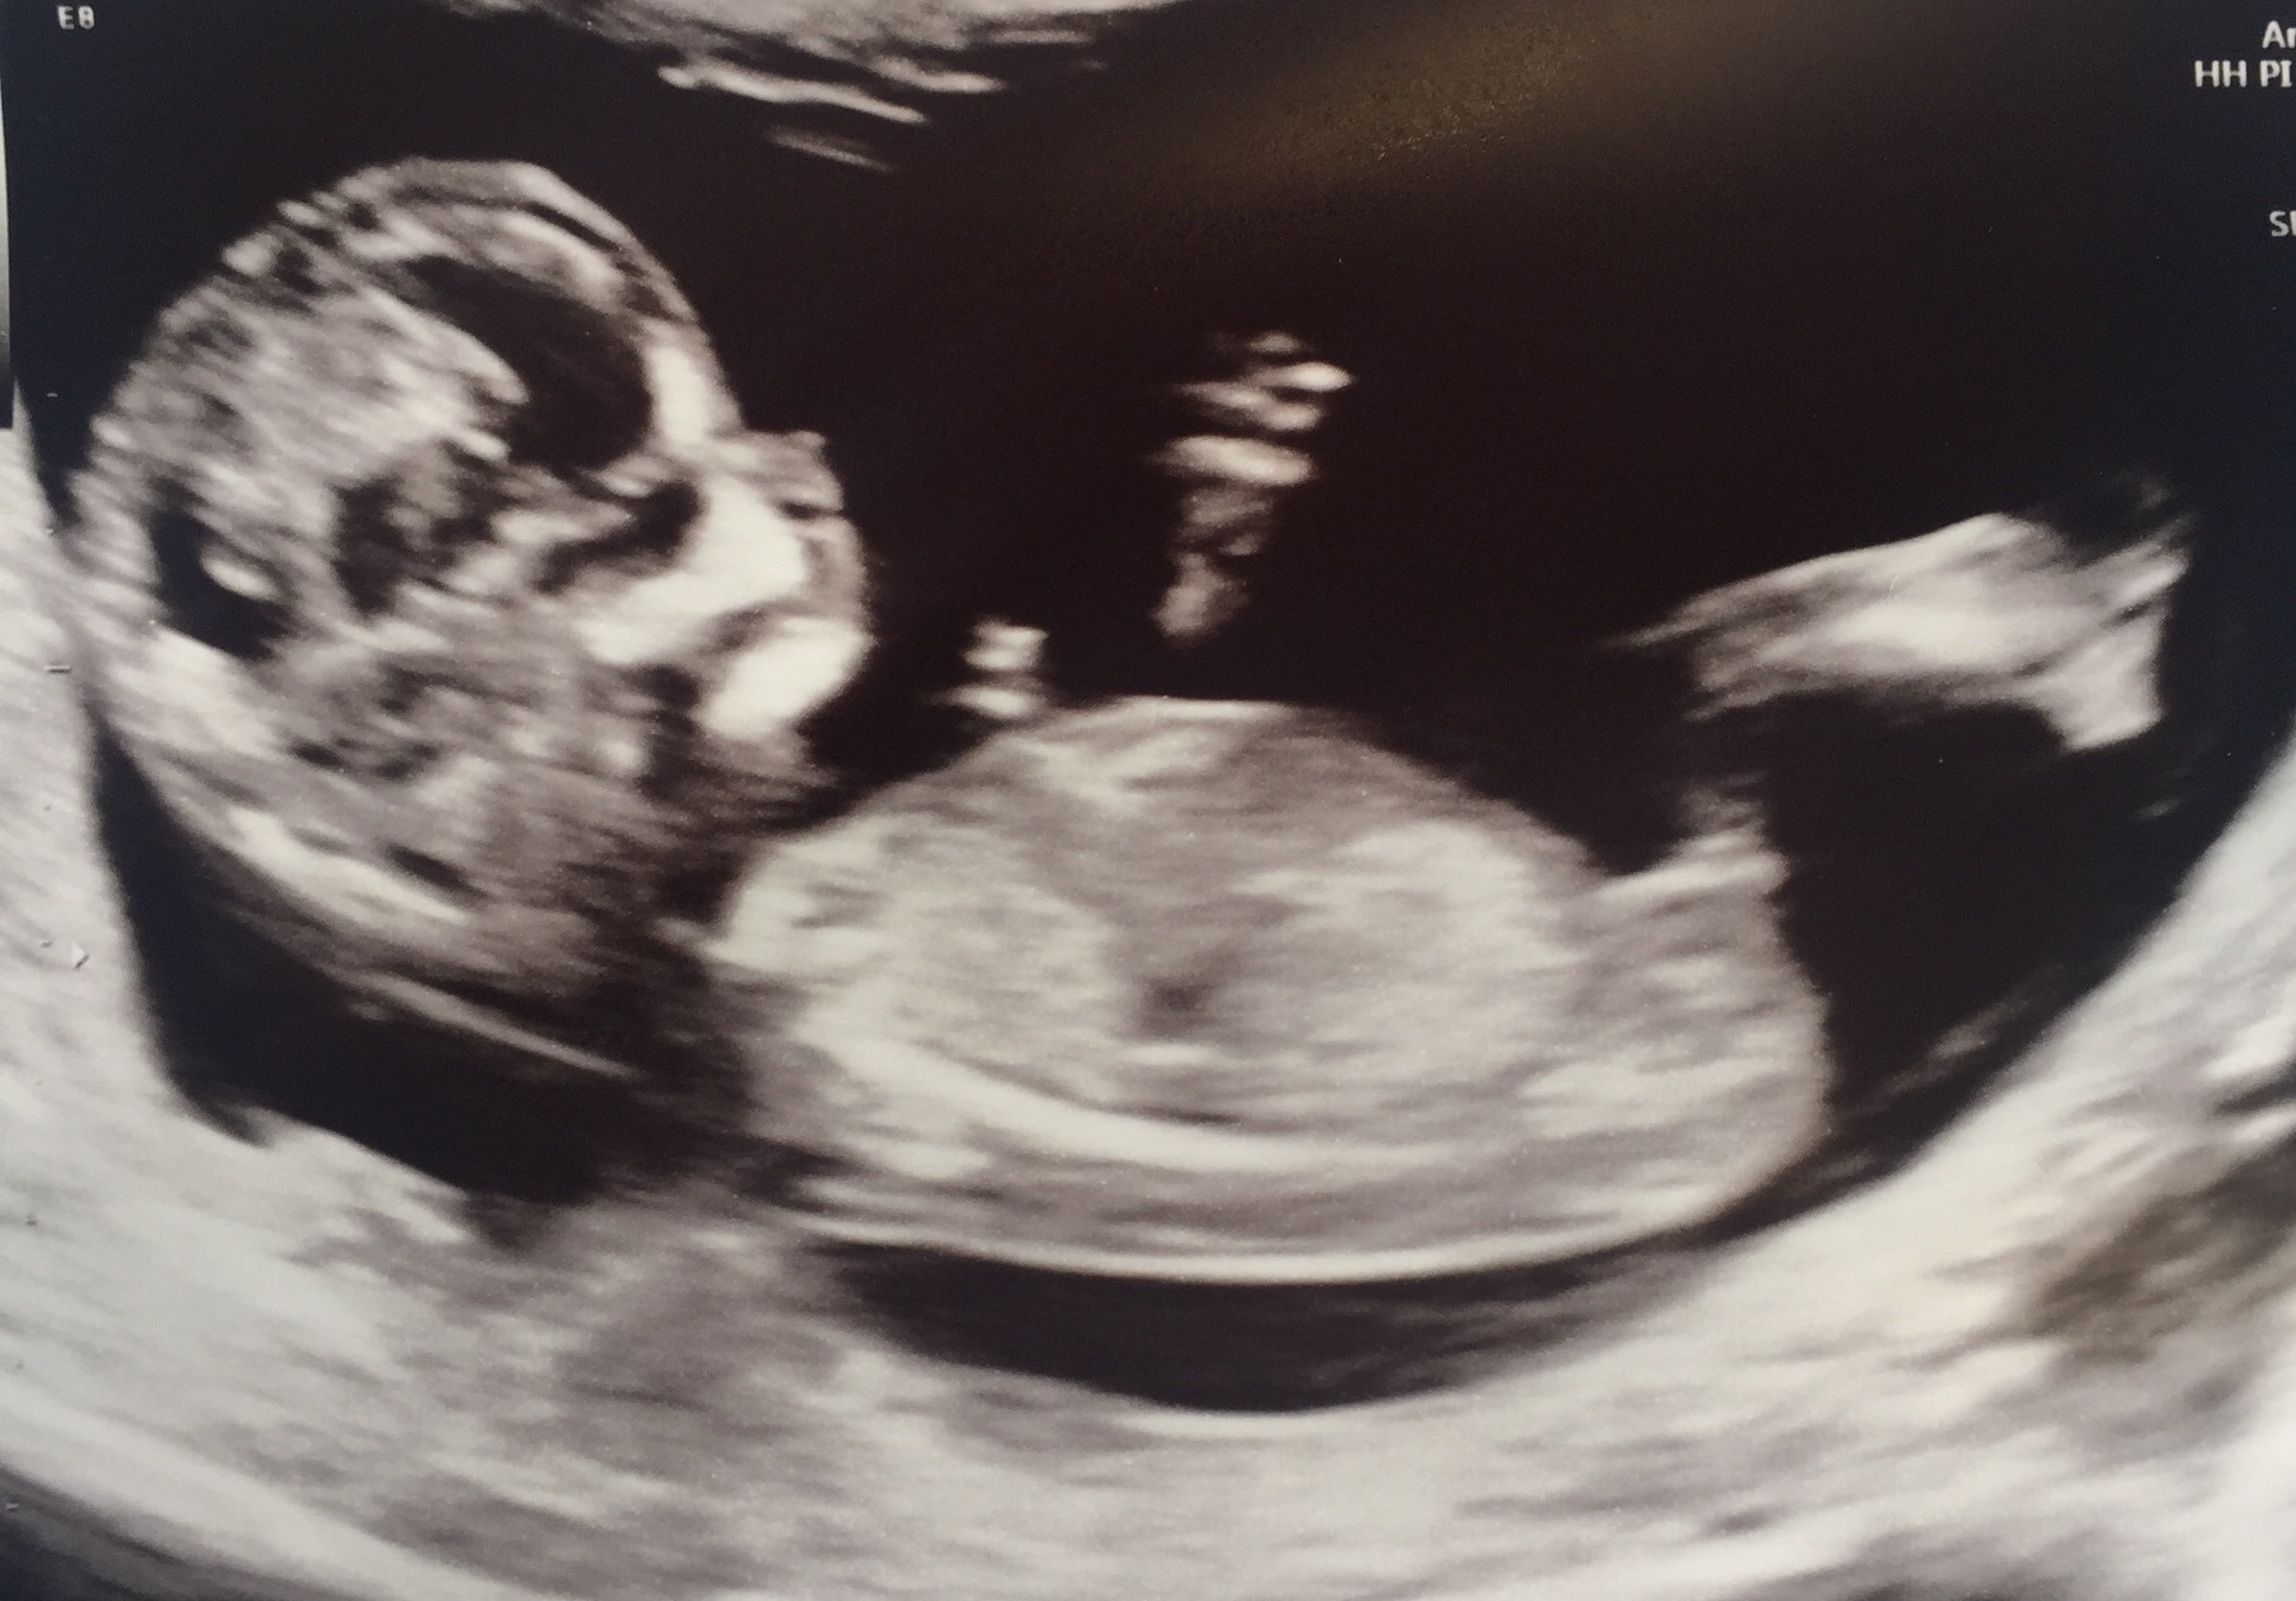

Hi ladies, 12+3 scan pics! Any help and guesses greatly appreciated! By looking at these photos I'm thinking it looks boyish but then also parallel with spine so maybe hope of a girl! I just don't know! XxAttachment 37858

Maybe boy? I think I see stacking in the second pic. The nub does look parallel with the spine but it's still early so still time for the nub to rise. Update us when you find out!